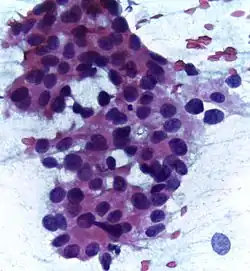

Infiltrative ductal carcinoma | Atypical cells with moderate amount of eosinophilic cytoplasm and round to oval dark nucleus with moderate pleomorphism (Papanicolaou, 400X) | Category: Histopathology of invasive carcinoma of no special type | invasive breast carcinoma |

![]() |